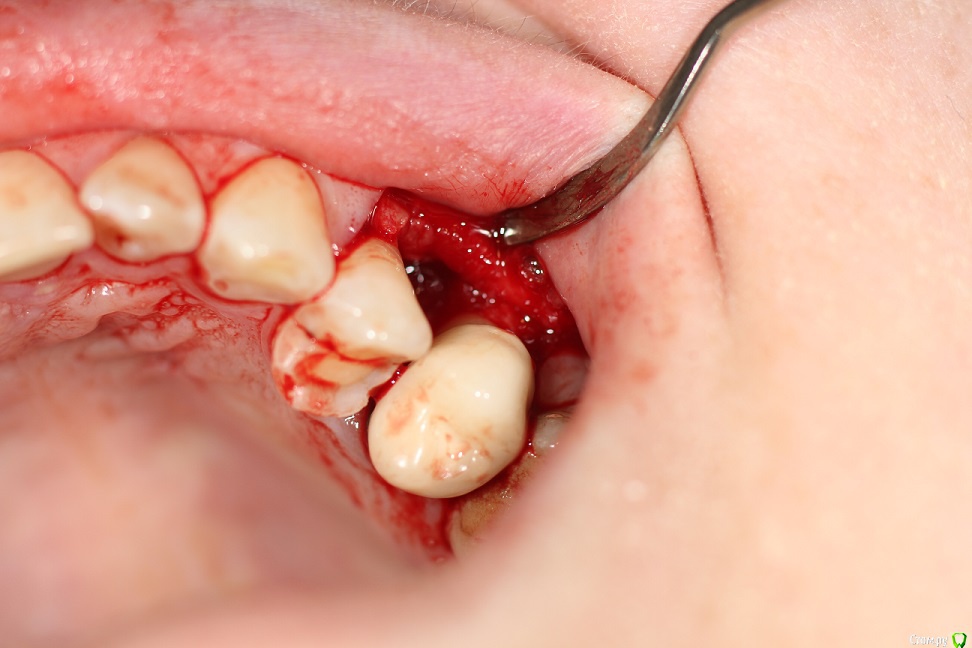

kuziy12 Опубликовано 22 февраля, 2020 Поделиться Опубликовано 22 февраля, 2020 Здравствуйте. Подскажите как лучше поступить. За качество фото извиняюсь, сел акум на основном. Телефон наше все.. Анамнез: 6 месяцев назад поставили мышьяк не очень герметично, неделю пациент ходил, так как не мог записаться. После попал ко мне. Эндо лечение зуба 2.5, удаление распада сосочка, добился крови из кости. Так как пациентка уезжала, постоянная коронка. Объективно:Межзубной сосочек отсутствует, секвестр подвижен, зуб 2.4 и 2.5 - подвижность I степени, перкуссия безболезненна. Сопр без особенностей. Вестибулярная кортикалка между зубами отсутствует. Зуб 2.4 живой. От себя: Если от мышьяка, то почему без острой стадии и как он так интересно подействовал в глубь кости, а не на поверхности? Точно не помню, но вроде в каналах пульпа была живая. Примерная тактика: откинуть лоскут, удалить секвестр, кюретаж. Имеет смысл подсыпать искусственную кость? Ссылка на комментарий

kuziy12 Опубликовано 8 марта, 2020 Автор Поделиться Опубликовано 8 марта, 2020 Как то так. Попытался вообще без откидывания, но тогда бы секвестр десну порвал, большой слишком. Уже его чуть сдвинул:Убрал грануляции:Ушился:Это секвестр: 3 Ссылка на комментарий